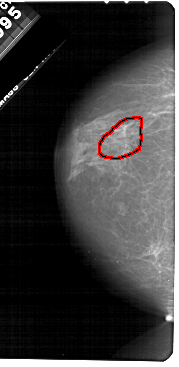

A_1651_1.LEFT_CC

LEFT_CC LINES 5491 PIXELS_PER_LINE 2671 BITS_PER_PIXEL 12 RESOLUTION 43.5 OVERLAY

FILE: A_1651_1.LEFT_MLO.OVERLAY

TOTAL_ABNORMALITIES 1

ABNORMALITY 1

LESION_TYPE CALCIFICATION TYPE PLEOMORPHIC DISTRIBUTION LINEAR

ASSESSMENT 4

SUBTLETY 1

PATHOLOGY BENIGN

TOTAL_OUTLINES 1

BOUNDARY